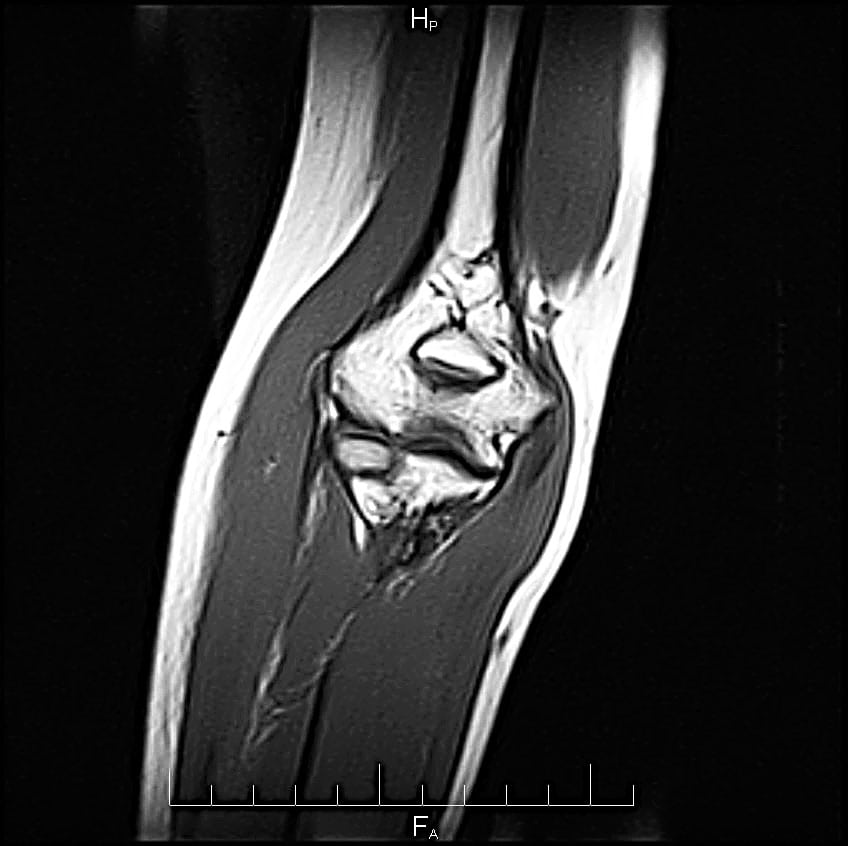

При выставлении диагноза врач учитывает результаты рентгенографии, МРТ, КТ, биохимических исследований крови, синовиальной жидкости. Лечение тендинита локтевого сустава проводится консервативными методами. Пациентам рекомендован прием НПВС, анальгетиков, физиотерапевтические процедуры, массаж, ЛФК. При неэффективности консервативной терапии показано хирургическое вмешательство с иссечением поврежденных тканей сухожилия.

- МРТ, КТ. Наиболее информативное исследование, помогающее установить степень повреждения тканей сухожилия, наличие островков жирового перерождения, локализацию и количество кальцификатов, фиброзных узелков.